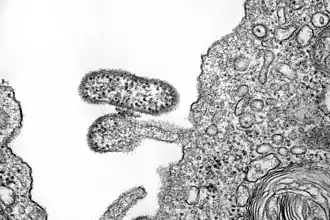

Das Chapare-Virus (CHAV, Art Mammarenavirus chapareense, früher Chapare mammarenavirus)[2][3] ist ein behülltes Virus mit einer einzelsträngigen, ambisense RNA als Genom, die in zwei geschlossenen Ringen (L- und S-Segment) im Virion vorliegt. Das Virus ist der Erreger eines Hämorrhagischen Fiebers mit einer Inkubationszeit von etwa 14 Tagen. Die Verbreitung des Virus ist noch unklar. Als Überträger dienen wie auch bei den nahe verwandten Viren sehr wahrscheinlich Nagetiere. 2019 wurde erstmals eine Übertragung von Mensch zu Mensch nachgewiesen.[4]